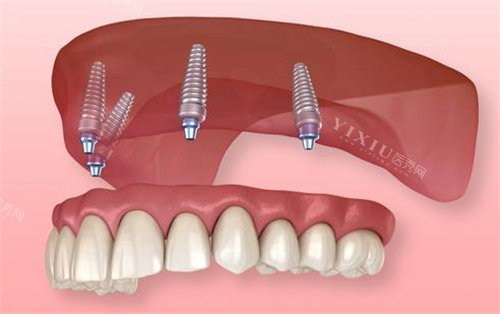

一、种植牙项目

国产种植牙:2870元起/颗

韩国DIO种植牙:3980元起/颗

韩国奥齿泰种植牙:4890元起/颗

瑞士ITI种植牙:5980元起/颗

瑞典诺贝尔种植牙:12800元起/颗

美国种植牙:9800元起/颗

半口种植套餐:50000元起

全口种植套餐:120000元起